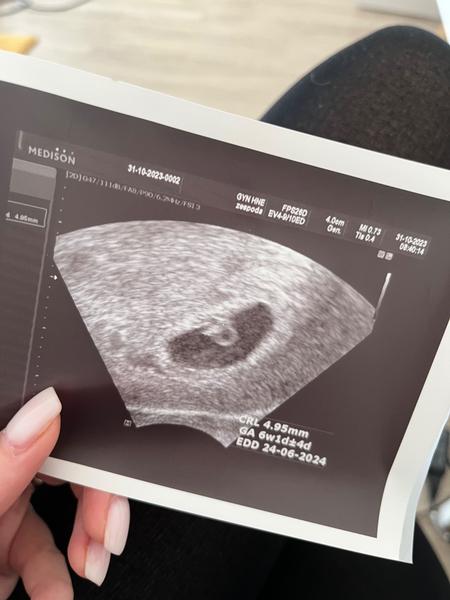

@milacek210 ahoj, minuly vikend jsem byla na pohotovosti kvuli spineni, ale vse ok. Pak hned v pondeli prvni kontrola u moji gyn v 6+1, srdecni akce byla, velikostne odpovida presne 😊 tak jen zobu utrogestan a odpocitavam dny do dalsi kontroly